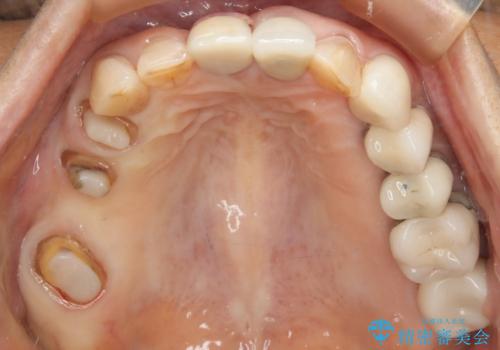

- 数十年前、アメリカで行った治療部位のやり直しを希望されてご来院。

ツギハギの修復が行われてきた被せ物は、縁が合っておらず隙間があり見た目も悪くなってしまっていました。

古い被せ物を除去し、中の状態をキレイにしたうえで改めて金属を使用していない被せ物で噛み合わせの回復を行いました。

被せ物の色は噛み合う反対側の被せ物と合わせて作りました。